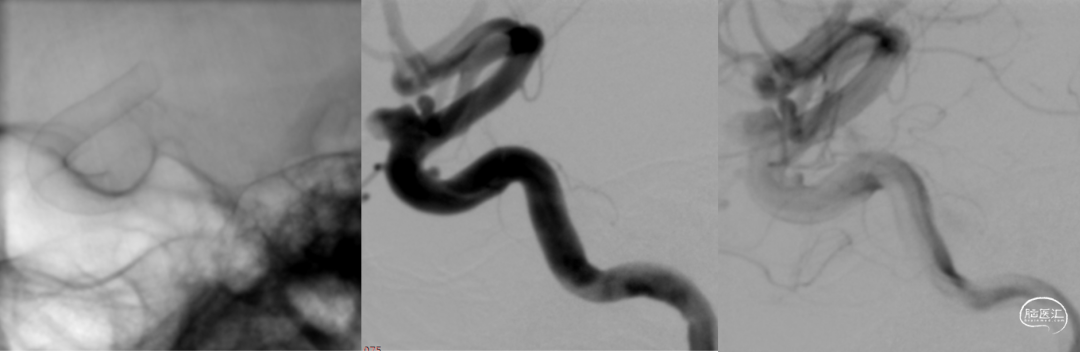

球囊后处理效果。

处理前

处理后